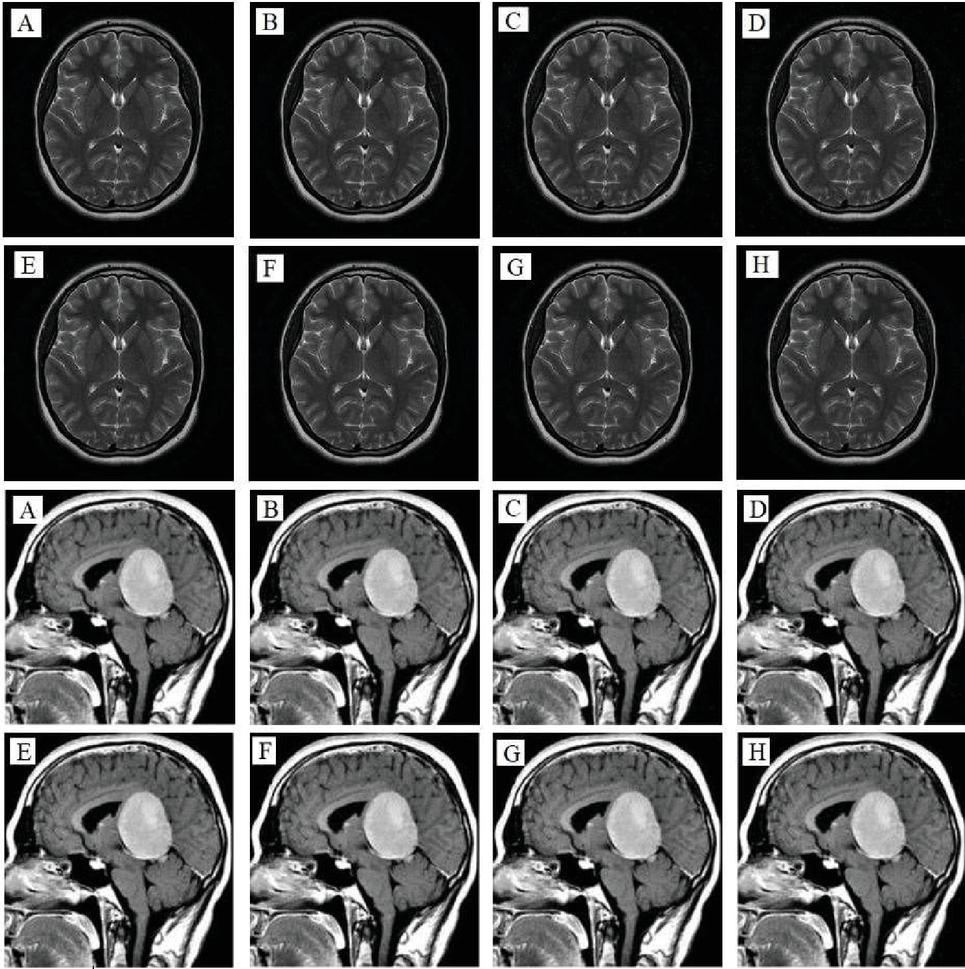

images

Figure 8 Depicts the outcome of the noise attacks test on Brain, and Meningioma 1 images, where (A)–(D) are the decrypted images after adding Speckle Noise with intensities of 0.000001, 0.000002, 0.000003, and 0.000004, respectively, and (E)–(H) are the decrypted images after adding Salt and Pepper Noise with intensities of 0.00001, 0.00003, 0.0005, and 0.0007, respectively.